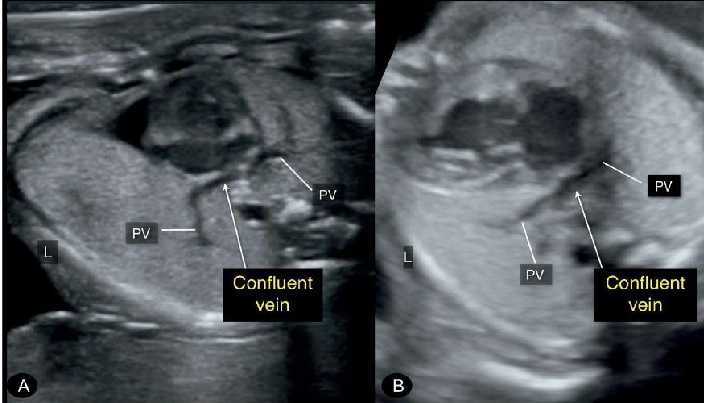

Hình 4: Mặt cắt ngang ngực 4 buồng tim. Thai nhi (A) và thai nhi (B) đều có bất thường hồi lưu tĩnh mạch phổi toàn phần (TAPVR). Lưu ý hình ảnh tĩnh mạch thu thập (confluent vein) ở phía sau tim nơi các tĩnh mạch phổi (PV) đổ vào, thay vì đổ vào tâm nhĩ trái. Ngoài TAPVR ở thai (A) còn có mỏm tim bên phải (dextrocardia) và kiểu hình bên phải (right isomerism), ở thai (B) còn có thiểu sản sản tim trái (hypoplastic left heart syndrome).